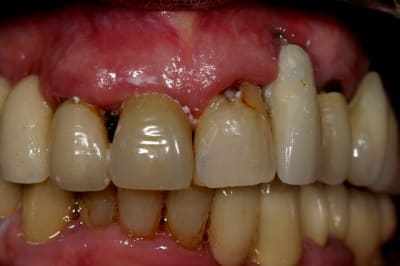

Voilà. Cette patiente se présente à moi. Elle est suivi depuis assez longtemps par un stomato. Qui l'a pris en charge pour la pose des implants que vous voyez sur la Pano.

Depuis deux ans cette patiente perd sa couronne sur 11. Vu l'état de la racine cela se comprend. Son praticien (sto) lui rescelle a chaque fois lui disant que l'on va s'en occuper...et cela tiens quelques jours au mieux.

Les implants maxillaire sont sous provisoires depuis au moins 8 mois. La dernière fois que j'ai vu la patiente je lui ai dit que l'on peut soir envisager un implant en position de 11, ou envisager un bridge 12-11-21 Car je pense que esthétiquement ce sera plus jouable...

Je l'ai informé qu'elle avait un gros soucis de carie sous les dents 47-46-45...Et que cela allez poser problème rapidement, mais que le site était propice au implants...